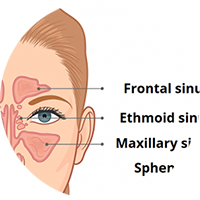

resonans.